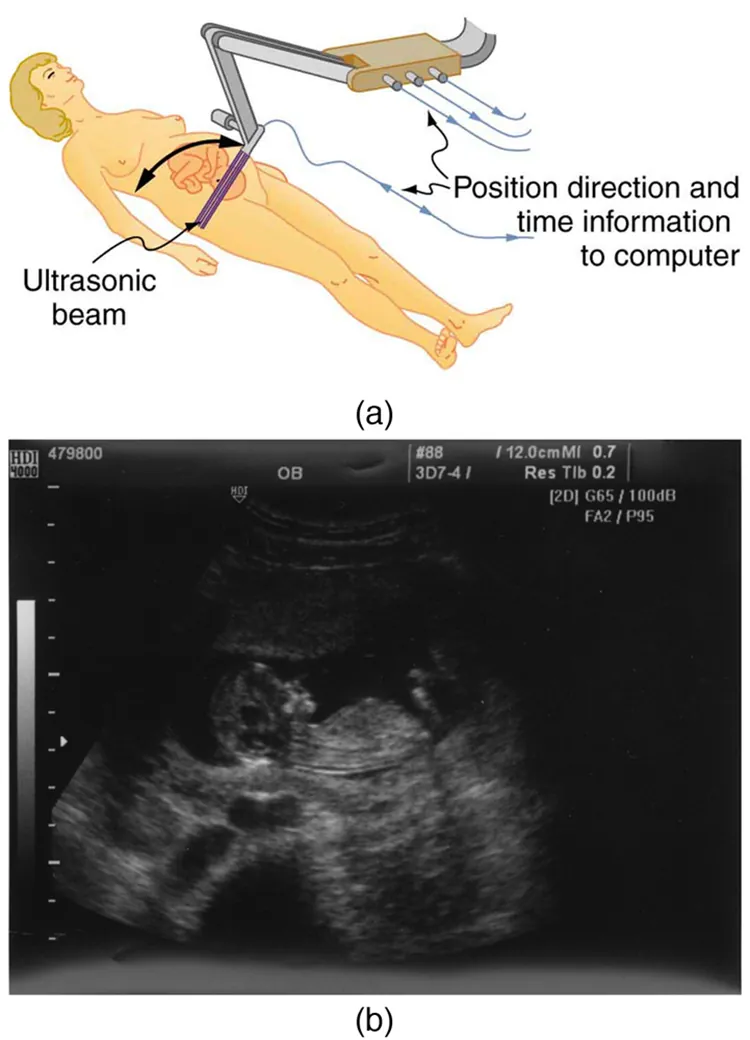

The most common ultrasound applications produce an image like that shown in Figure 17.44. The speaker-microphone broadcasts a directional beam, sweeping the beam across the area of interest. This is accomplished by having multiple ultrasound sources in the probe’s head, which are phased to interfere constructively in a given, adjustable direction. Echoes are measured as a function of position as well as depth. A computer constructs an image that reveals the shape and density of internal structures.

The first part of the diagram shows an ultrasound device scanning a woman’s abdomen. The second part of the diagram is an ultrasound scan report of the abdomen.

Figure 17.44 (a) An ultrasonic image is produced by sweeping the ultrasonic beam across the area of interest, in this case the woman’s abdomen. Data are recorded and analyzed in a computer, providing a two-dimensional image. (b) Ultrasound image of 12-week-old fetus. (credit: Margaret W. Carruthers, Flickr)

How much detail can ultrasound reveal? The image in Figure 17.44 is typical of low-cost systems, but that in Figure 17.45 shows the remarkable detail possible with more advanced systems, including 3D imaging. Ultrasound today is commonly used in prenatal care. Such imaging can be used to see if the fetus is developing at a normal rate, and help in the determination of serious problems early in the pregnancy. Ultrasound is also in wide use to image the chambers of the heart and the flow of blood within the beating heart, using the Doppler effect (echocardiology).